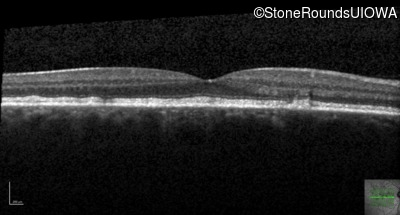

Optical Coherence Tomography - Right - 20/40 +2 sc

Exemplar / OCT Stack

OCT Stack

Optical Coherence Tomography - Left - 20/40 +1 sc